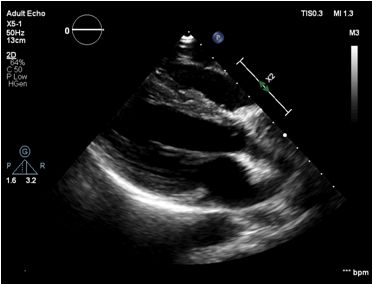

重症彩超

1、下腔静脉变异度8%

2、左心收缩功能:EF=57%FS=30% EDV=111ml SV=64ml

左室舒张功能降低